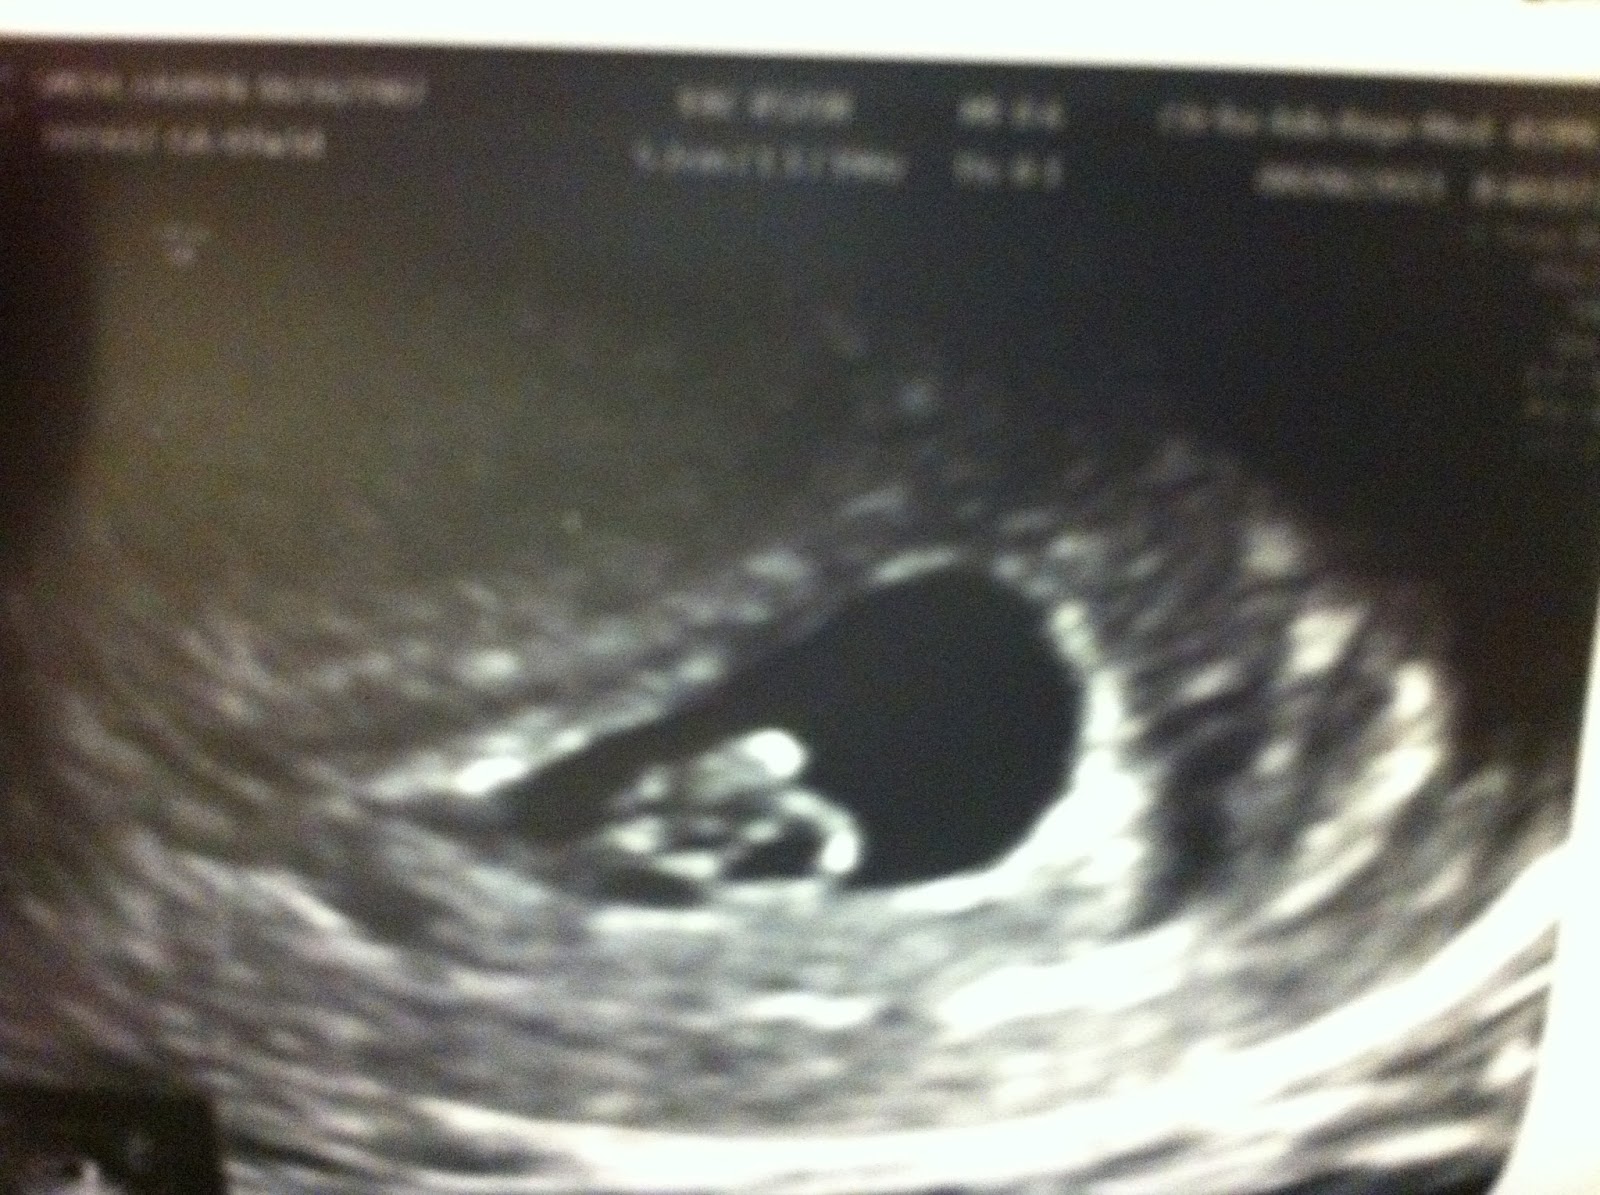

Tuesday was our 2nd ultrasound. We get to have one more next week and then we have to wait awhile for our next. (around 12 weeks I believe). This is part of our close out requirements from the infertility clinic. 7 days after our first look at our baby and we were SHOCKED to see how much it has grown. About triple the size it was last week and looks more like a baby instead of a dot. Either way it's heart was beating strong at 134 bpm (108 last week). The sonographer and nurse said everything looked perfect and scheduled us for our close out appointments with our reproductive endocrinologist. Next Wednesday our RE will do our longer more comprehensive sono and will talk with us in her office about our experience and our questions, concerns and comments and if everything looks good we will have our first appointment with my new OB/GYN and maybe another sono if we are lucky! The appointments with both doctors are 1 day a part and I am hoping that they can tell us how baby is measuring compared to our estimated due date and set an actual due date for us. Here are the pics of the baby this week and the last is the comparison from this week and last.

The baby is the blob on top inside the dark circle.